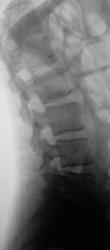

Нижняя замыкательная пластинка L5 "некрасивая", возможно грыжа диска L5-S1.

Жалобы обычные - боль в пояснице, особенно при разгибании. Да в одной из ягодиц "точку седалищного" ощущает...

Возможно, стоит грыжу на МРТ поискать. Или если мужчина молодой, присмотреться к крестцово-подвздошным суставам (в плане дебюта спондилоартрита).